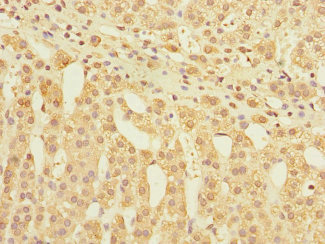

圖片:

應(yīng)用范圍:ELISA, IHC

Application Recommended Dilution IHC 1:20-1:200 -